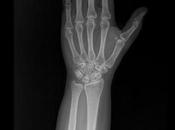

Fractura de estiloides de radio con involucro intraarticular (fractura de chofer)

RADIOGRAFIAS AP DE MUÑECA Hallazgos: -Apófisis estiloides de radio, con pérdida de la contigüidad por trazo oblicuo con involucro intraarticular, sin... Leer el resto

El 03 enero 2025 por Godieboy